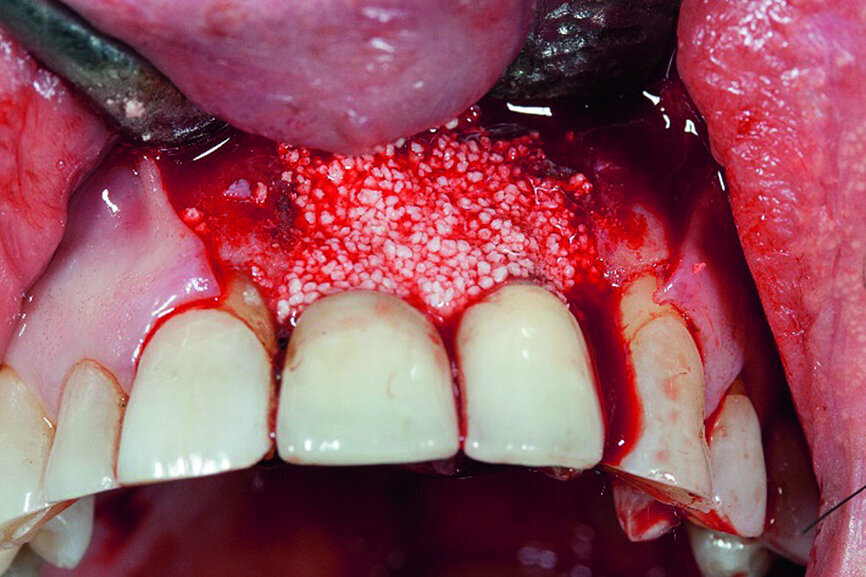

After completion of the preparatory steps, the bone replacement material consisting of phase-free beta-tricalcium phosphate—which offers optimal conditions for osseous remodelling owing to its micro-, meso- and macropores—was inserted as previously described (Fig. 7).